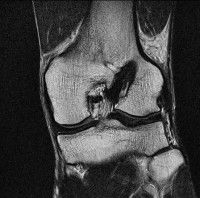

무릎 mri 간단히 봐주실 수 있으시나요 ㅠㅠ

안녕하세요 8년전 십자인대 수술하고 최근 무리한 운동에 무릎 불편감이 생겨서

mri 찍었습니다.

진단결과는 첫 찍은 병원에서 활액막염 이라는 진단을 받았습니다. 혹시 봐주실 수 있으실까요?

올라온 MRI가 단편적이라서 정확한 진단에 어려움이 있지만 십자인대에는 큰 이상이 있지는 않은것 같으며, 무릎관절내 물이 있는 것으로 보아 활액막염의 진단이 맞을 것 같습니다.

하지만 단편적인 영상이기 때문에 촬영병원에서 정확한 판독지 등을 받으시는 것이 좋겠습니다.